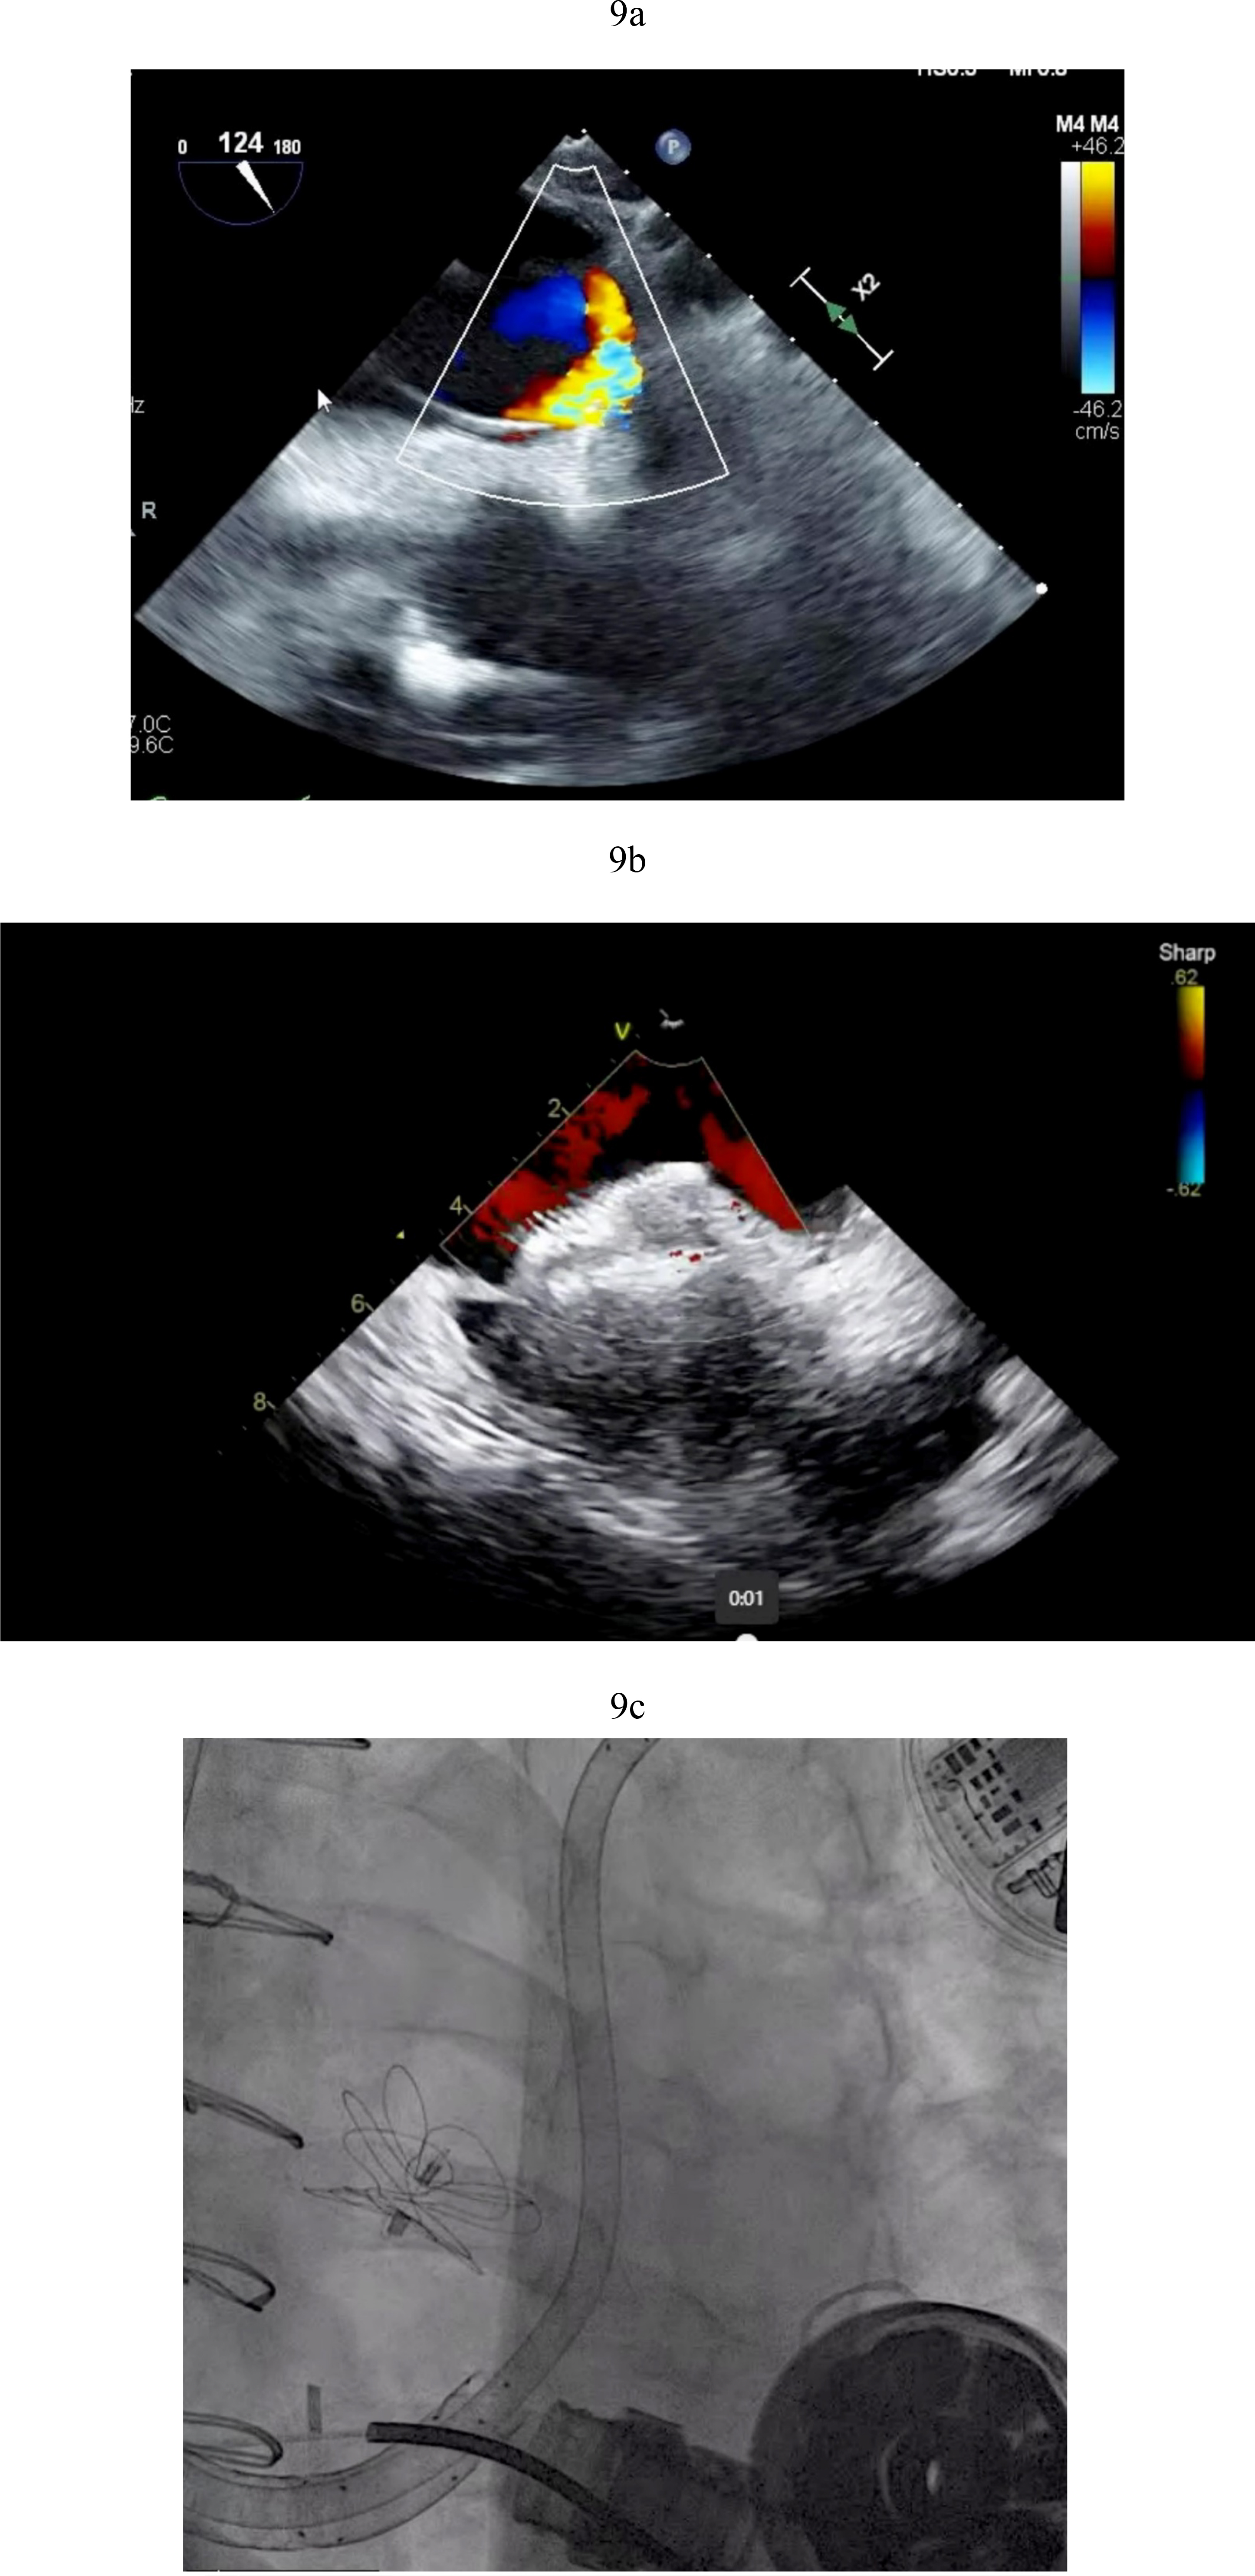

The determination of what is significant is driven by two factors. The size of the defect certainly plays a role but more importantly one needs to consider that RV dysfunction and elevated right -sided filling pressures may occur post LVAD in the immediate post operative state. PFOs can become very problematic in circumstances of significant RV failure post LVAD. As right atrial pressures rises, right to left shunting increases (Fig. 9a). This shunting can result in hypoxemia that worsens pulmonary vascular resistance and leads to worsening right ventricular function with further increases in right atrial pressures. This vicious cycle can quickly derail a stable post-operative course. Percutaneous PFO closure can effectively stop right to left shunting and ameliorate symptoms (Fig. 9b). In situations where right ventricular hemodynamics are tenuous, compromising LVAD preload and flows and jeopardizing end organ function, RVADs may be required to stabilize the patient’s condition prior to PFO closure (Fig. 9c).

Fig. 9. PFO closure post LVAD. (a) Large right to left shunt in a patient with PFO and RV failure. (b) Amplatzer closure of PFO in LVAD patient. (c) Successful closure of PFO with Gore 32 mm ASD occluder. Patient on RVAD support due to worsening RV failure in the settting of hypoxemia. RV, right ventricular; RVAD, right ventricular assist device.